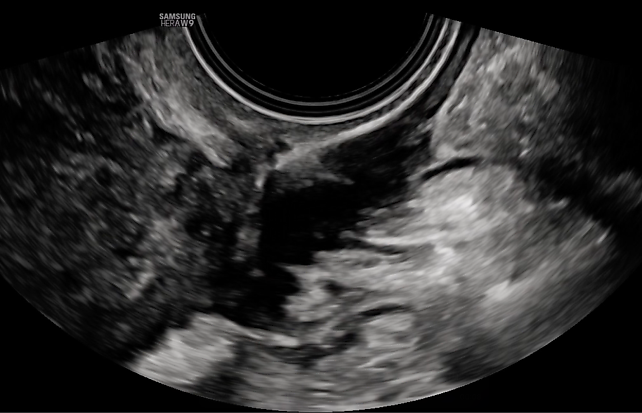

2

Ultrasound image showing an enlarged globular uterus, with diffuse fan-shaped shadowing and an irregular junctional zone. This is indicative of severe diffuse adenomyosis, Type 1–3.